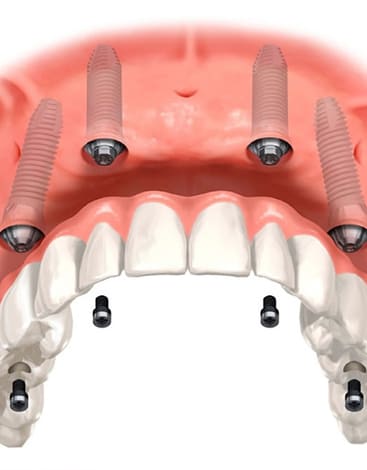

祐天寺歯科では、歯を失った際の治療法の一つとしてインプラント治療をおすすめしております。当院では患者さまが不安なく治療に臨めるよう、インプラントの無料相談をはじめ、CTでの精密検査など、手術時のトラブル軽減はもちろん、審美性や長持ちにこだわった精密なインプラント治療に努めております。

インプラント手術を実施する際は、事前にCTによる精密検査を行います。

インプラント手術では、オペ専用ルームを完備

負担の少ない特殊なインプラント治療にも対応